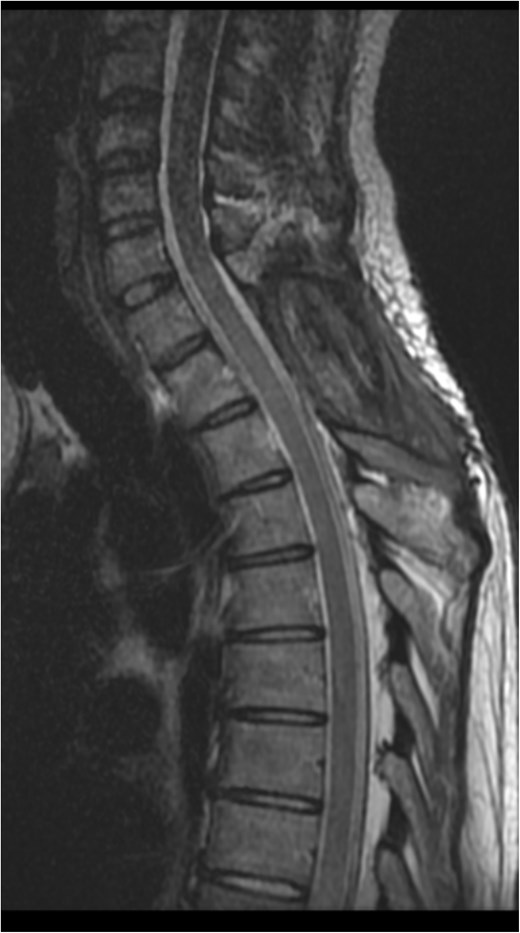

The postoperative plan included early mobilization, sensory and balance training, progressive gait exercises, and follow-up imaging (DSA or MRA) to rule out missed pathological vessels. Neurological function improved, with motor strength rated 4/5 in the left leg and 3/5 in the right. Postoperative imaging was satisfactory, with no evidence of spinal cord compression as shown in Fig. 2. The patient was advised to continue occupational therapy for lower limb strengthening and physiotherapy to ensure safe ambulation.

Eight months postoperative T2-weighted sagittal views MRI of the cervical spine.